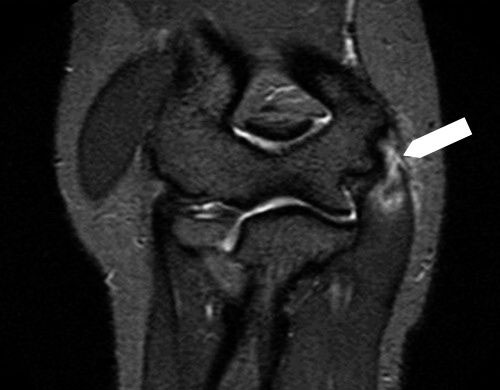

If conditions other than golfer’s elbow are suspected, the following examinations may be performed for differential diagnosis. Among these, magnetic resonance imaging (MRI) and ultrasonography (ultrasound examination) are considered the most effective.

MRI image showing golfer’s elbow, indicated by the white area marked with an arrow.